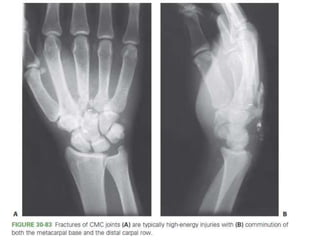

Carpometacarpal (CMC) Fractures

Carpometacarpal (CMC) Fractures •The normal ROM at the thumb CMC joint • 50 degrees of flexion-extension • 40 degrees of abduction-adduction • 15 degrees of pronation-supination.